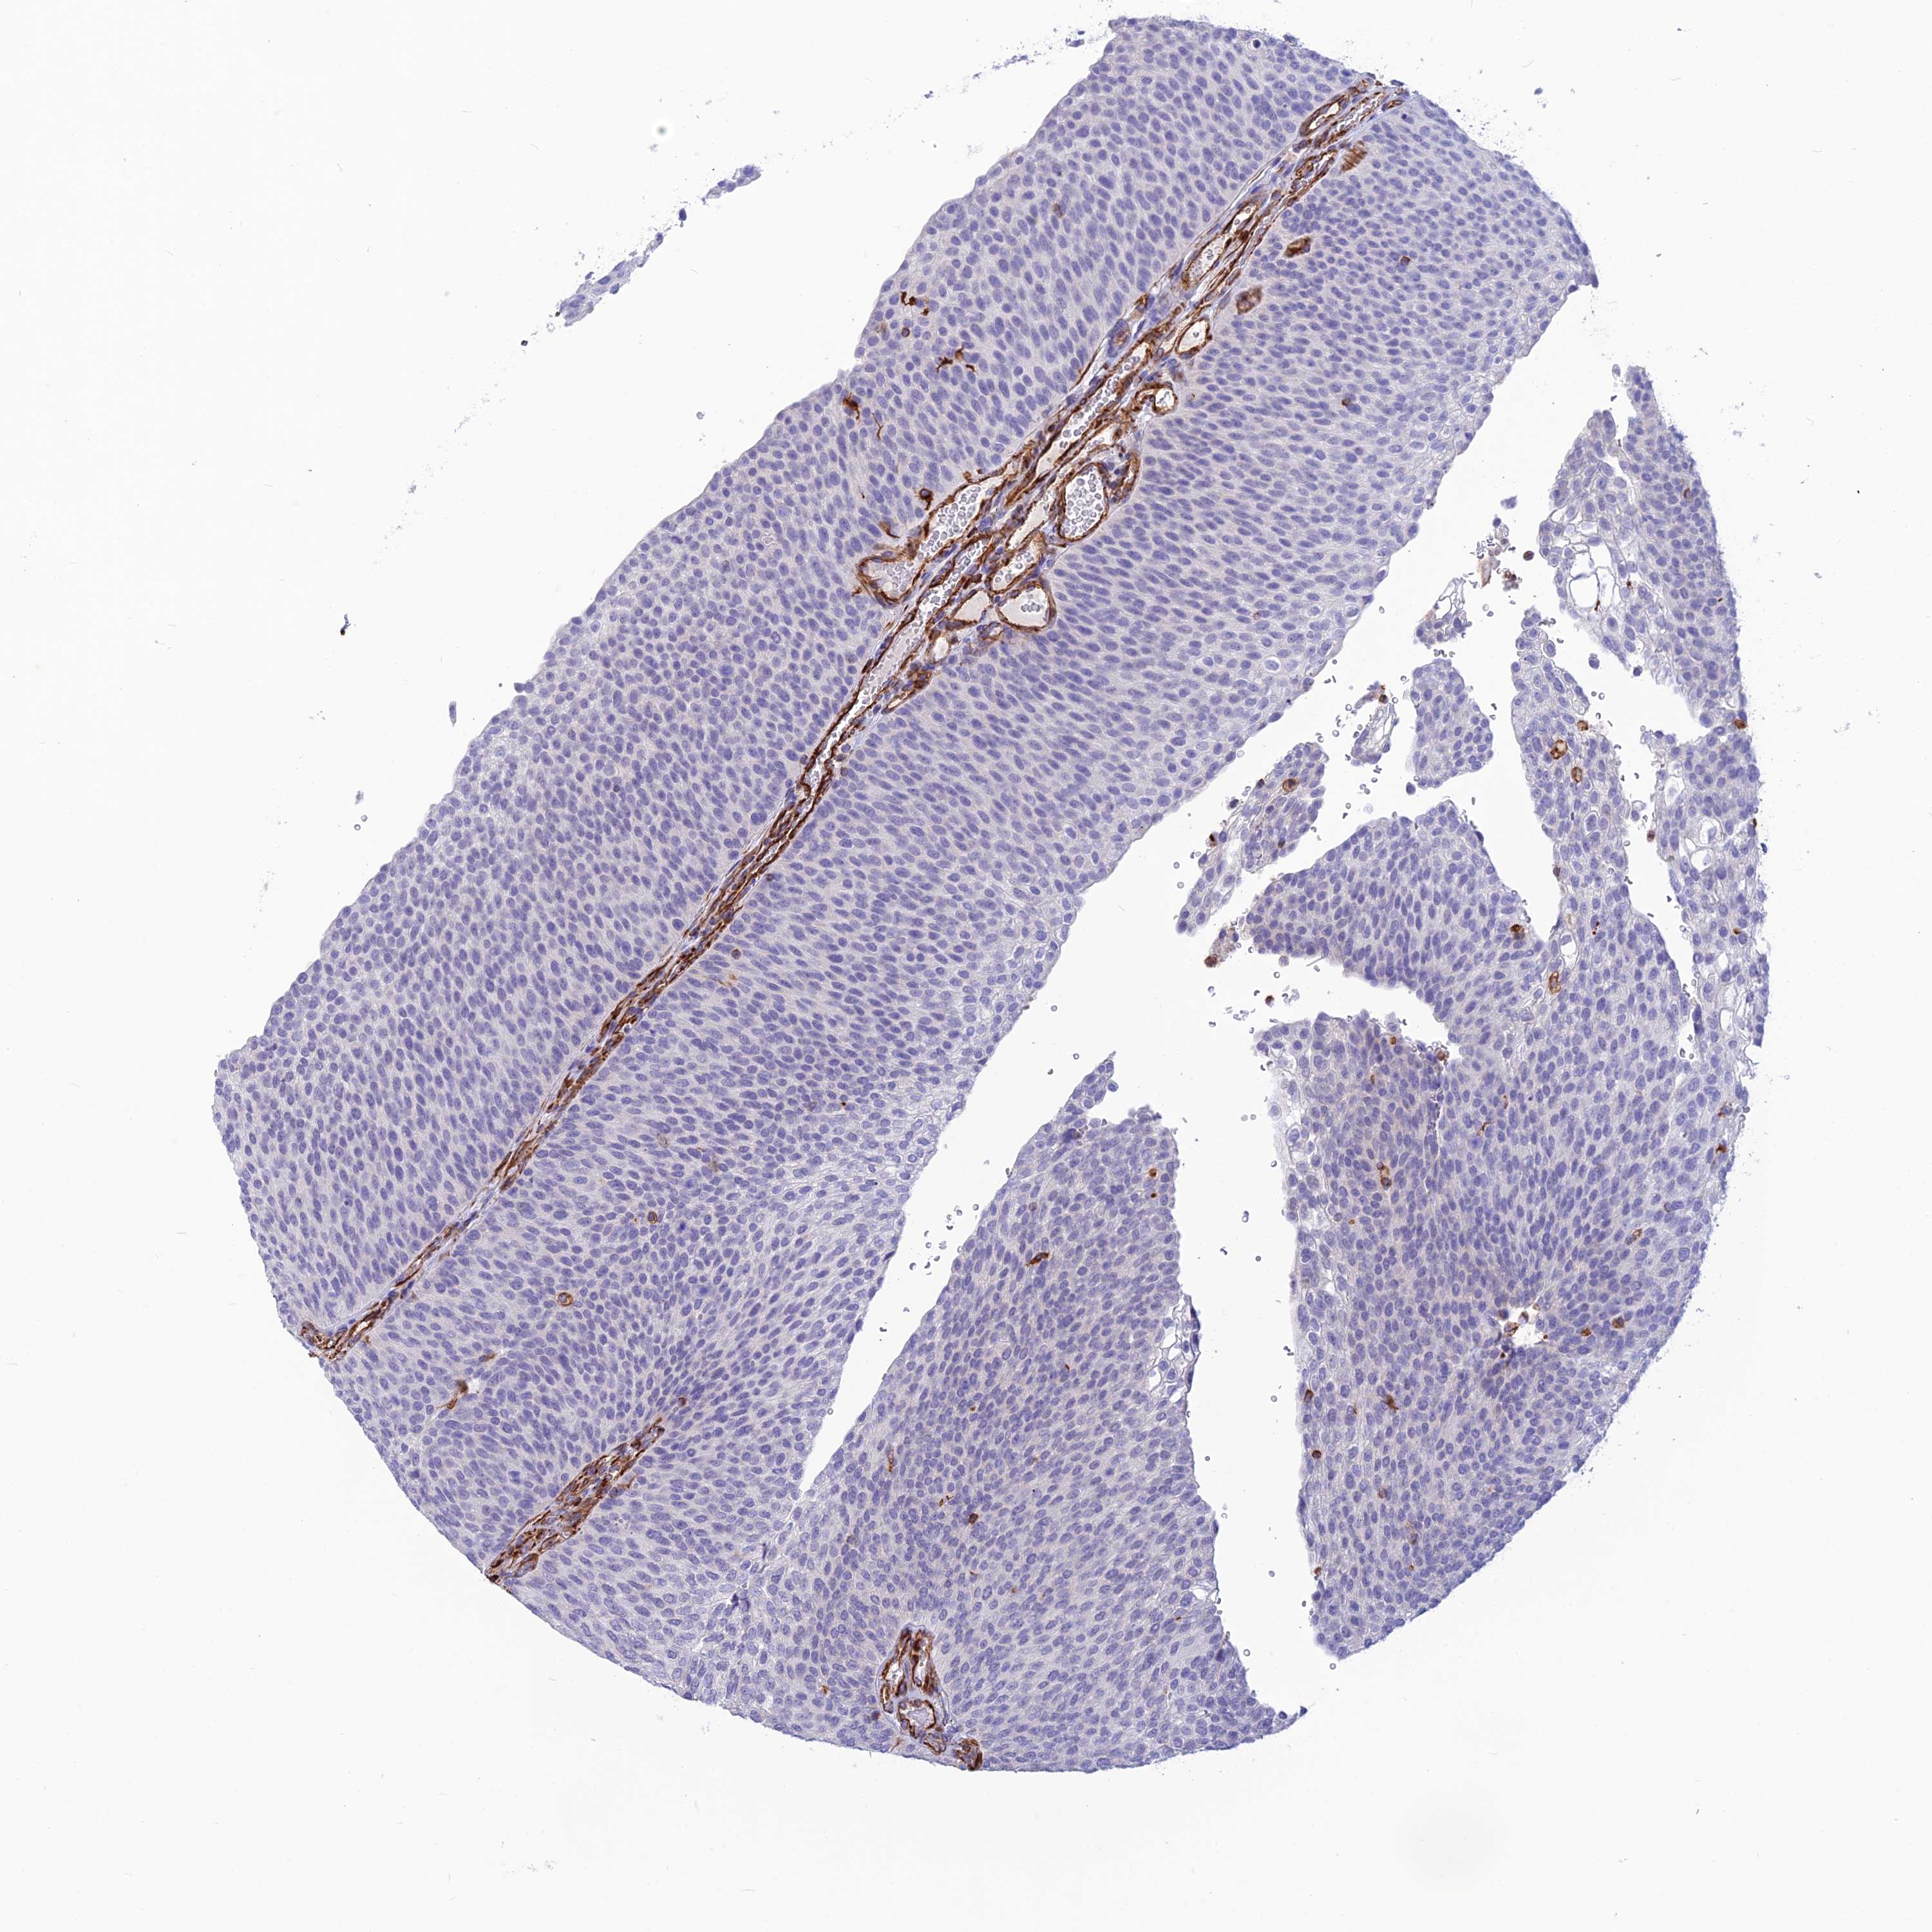

UROTHELIAL CANCER - Protein expressioni

A mouse-over function shows sample information and annotation data. Click on an image to view it in a full screen mode. Samples can be filtered based on level of antibody staining by selecting one or several of the following categories: high, medium, low and not detected. The assay and annotation is described here.

Note that samples used for immunohistochemistry by the Human Protein Atlas do not correspond to samples in the TCGA dataset.

Antibody stainingi

Antibody staining in the annotated cell types in the current human tissue is reported as not detected, low, medium, or high, based on conventional immunohistochemistry profiling in selected tissues. This score is based on the combination of the staining intensity and fraction of stained cells.

Each image is clickable and will lead to virtual microscopy that enables deeper exploration of all samples and also displays staining intensity scores, fraction scores and subcellular localization as well as patient and tissue information for each sample.

Antibody HPA044748

Antibody HPA050397

Urothelial carcinoma, High grade

Urothelial carcinoma, Low grade